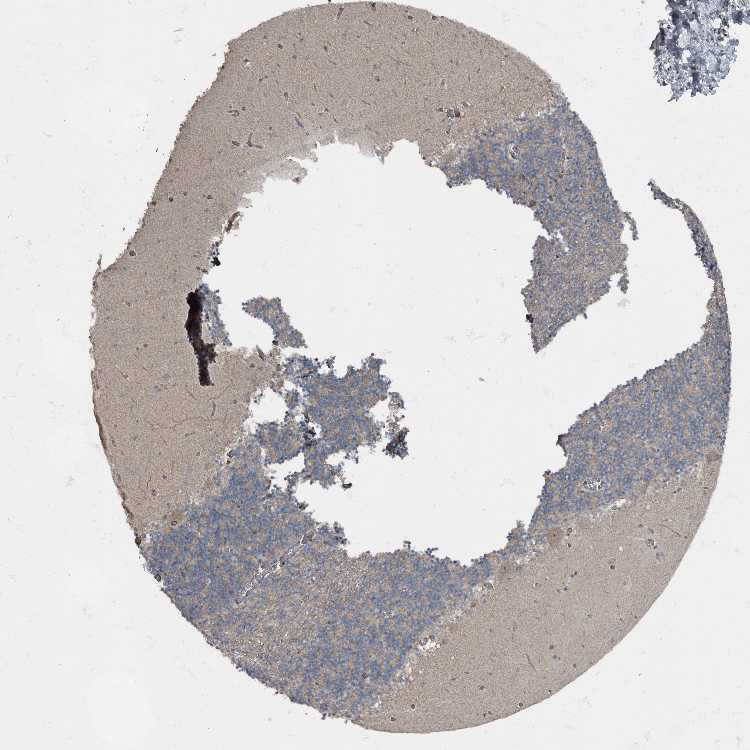

CEREBELLUM - Antibody stainingi

Antibody staining in the annotated cell types in the current human tissue is reported as not detected, low, medium, or high, based on conventional immunohistochemistry profiling in selected tissues. This score is based on the combination of the staining intensity and fraction of stained cells.

Each image is clickable and will lead to virtual microscopy that enables deeper exploration of all samples and also displays staining intensity scores, fraction scores and subcellular localization as well as patient and tissue information for each sample.

Antibody HPA026585Antibody HPA027167

Purkinje cells - cytoplasm/membrane Medium-

Molecular layer cells - cytoplasm/membrane Medium-

Synaptic glomeruli - core High-

White matter cells - cytoplasm/membrane Medium-